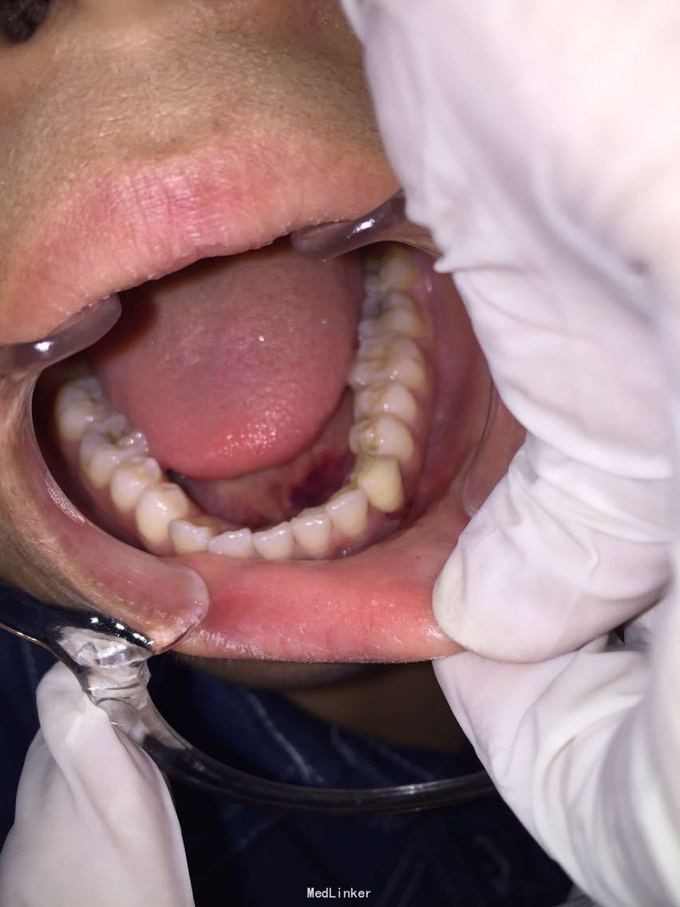

牙脱位24小时要求处理 昨晚8点吃铁板烧的时候咬到硬物致左下尖牙脱落到铁板烧中污染,取出牙齿用纸巾保存,第二天到就近医院处理,医生建议其做种植牙修复或烤瓷桥修复,脱落牙齿无法保留,患者又陆续问了4家医院都无法保留脱落牙齿,晚上8点找到我院(夜班8点下班)要求处理。

D3完全脱位,伤口血凝块已经凝固,颊侧牙龈钝性撕裂。D2D4无叩痛和松动。脱落牙齿牙体硬组织完好,牙周膜干裂,牙体上有纸屑和食物残渣,根尖有牙髓组织呈黑红色。